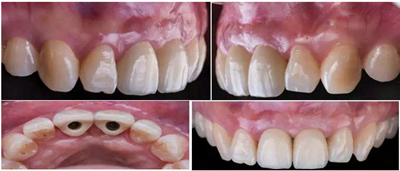

過渡義齒制作完成及試戴

過渡義齒佩戴3個(gè)月后

根據(jù)過渡義齒的螺絲孔及開口位置,最終修復(fù)方式為個(gè)性化全瓷基臺(tái)+全瓷冠。由于粘接界面位于齦下,粘接劑殘留可能會(huì)誘發(fā)種植體周圍發(fā)炎發(fā)生,因此本病例首選螺絲固位的方式。

角度螺絲通道全瓷基臺(tái)一體冠制作(機(jī)械連接,無粘接劑;原廠配件;更好的穿齦形態(tài);方便取下維護(hù))。

種植過渡義齒是醫(yī)技患三者共同合作的結(jié)果,通過觀察過渡義齒的形態(tài)、牙齦袖口、咬合等,為最終義齒修復(fù)奠定了基礎(chǔ)。本案例經(jīng)醫(yī)技患三方溝通討論,最終確定治療方案:Asc角度螺絲通道全瓷基臺(tái)一體冠進(jìn)行種植固定修復(fù)。

角度螺絲通道全瓷基臺(tái)一體冠制作完成